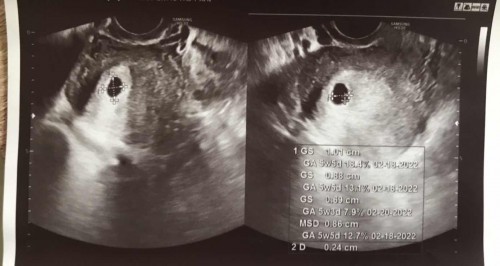

Hello! Today was my baby’s first ultrasound. Im 5 weeks pregnant. But I am worried, ung report po kasi sa ultrasound may nakalagay sa right side na Gravida Para Ectopic Aborta? Ano po meaning nun? 🥺#pleasehelp #pregnancy #pleasehelp #pleasehelp